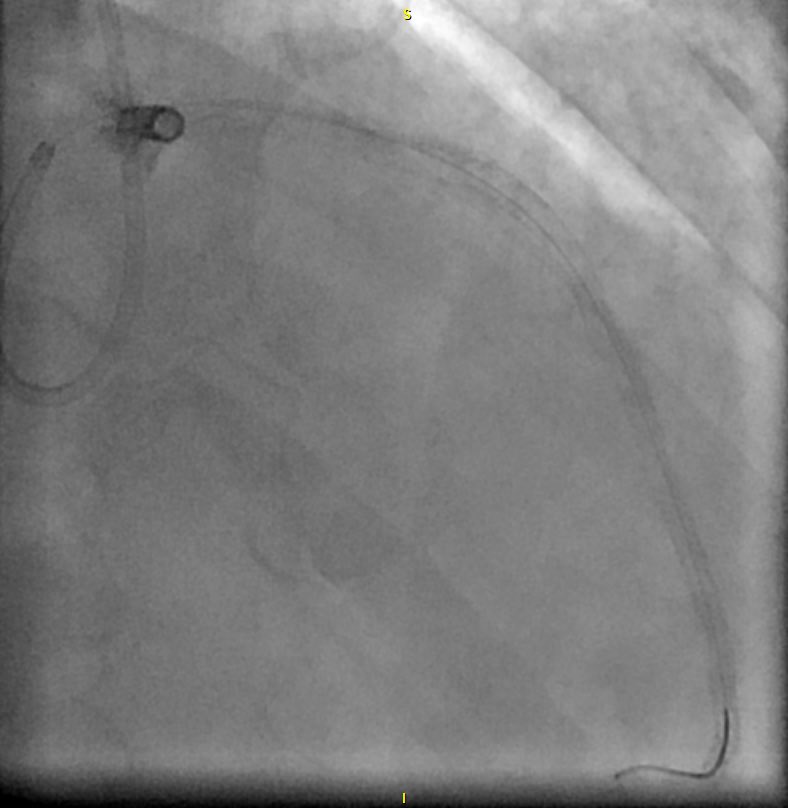

Looking at a CTA to assess candidacy for robotic mitral repair. What’s the abnormality?

3